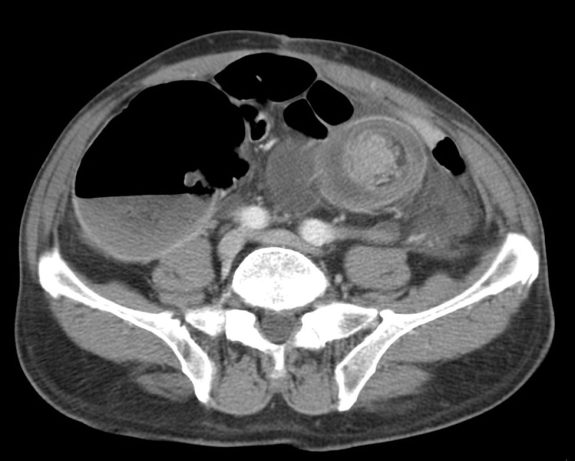

Imagen radiologica:

El método de elección es la TC, ya que, si bien existen otras técnicas diagnósticas (como la radiografía simple, el enema de bario o la ecografía), ninguna presenta una sensibilidad y especificidad tan elevadas en la poblacion adulta.

- El hallazgo patognomónico es el signo de la escarapela o diana identificable en la TC o ecografía.

- Podemos ver la imagen de «Intestino dentro de intestino” gracias a las reconstrucciones multiplanares.